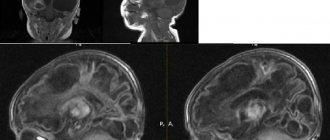

Томограммы эпидуральных гематом

Что покажут снимки КТ головного мозга при наличии эпидуральной гематомы

- Двояковыпуклая форма

- Гиперденсная

- Свежая несвернувшаяся кровь может быть также гиподенсной

- Гематома не пересекает линии швов, так как твердая мозговая оболочка плотно сращена с костями свода черепа по ходу границ между ними

- Выраженное объемное воздействие: смещение срединных структур

Компьютерная томография – эффективный метод диагностики. Образования в эпидуральном пространстве имеют двояковыпуклую форму. Их типичный район локализации – височная кость (os temporale), а именно – чешуйчатая часть(pars squamosa). Они представляют собой участок ткани с пониженной плотностью.Структура гематом неоднородная. Границы образования нечеткие.